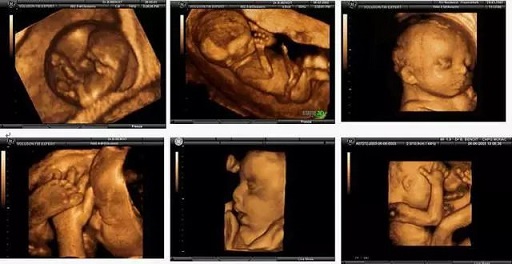

• 為何四維彩超如此受孕媽歡迎

為何四維彩超如此受孕媽歡迎

孕媽正在長沙百佳瑪麗亞婦產(chǎn)醫(yī)院做四維彩超。  四維彩超這項(xiàng)孕期必檢項(xiàng)目孕媽圈無人不知,之所以能在產(chǎn)檢項(xiàng)目中脫穎而出,不僅因?yàn)樗蚱屏藗鹘y(tǒng)B超黑白圖像的沉悶,更重要

寶寶的第一張照片:四維彩超,孕媽媽們了解一下吧

親貝網(wǎng)小編了解到,懷孕以后,準(zhǔn)媽媽都很關(guān)心腹中胎兒的發(fā)育情況,每當(dāng)看到其他準(zhǔn)媽媽曬的胎兒四維彩超的照片和錄像,心都要被萌化了,也想做一次四維彩超。那么有關(guān)四維彩超的知識,你知道嗎,一起來了解一下吧。

孕檢必須要做四維嗎?結(jié)果可能讓你想不到

普通B超拍的是黑白圖片,彩超拍的是彩色照片,三維彩超是給彩色圖片做了3D建模,四維彩超則是在3D建模的基礎(chǔ)上加了動(dòng)畫特效??偠灾?,普通B超和彩超的區(qū)別,就是黑白照片和彩色照片的區(qū)別。彩超應(yīng)用廣泛,是因?yàn)楦菀卓辞逄河袥]有出現(xiàn)臍帶繞頸。